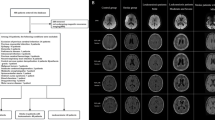

As shown in Table 1, a total of 460 consecutive TIA patients upon arrival to the medical facility were included in the analysis with a mean age of 71.4 (SD 13.6) years, 221 (48.0%) patients were female. A total of 37 (8%) patients suffered SR after 90 days follow-up (Fig. 1), of whom 23 were females (62.2%).